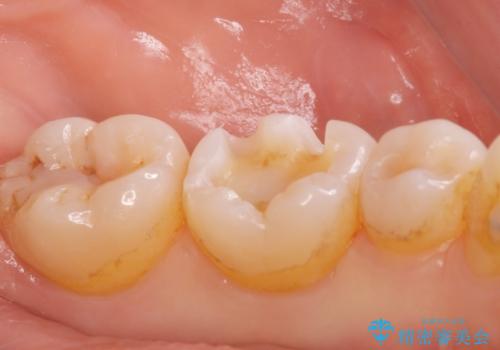

白い詰め物が入り患者様に満足してもらいました。